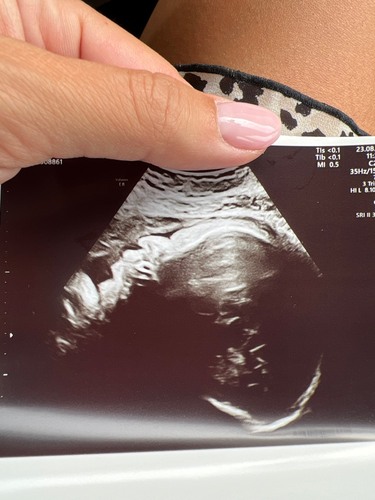

Echo’s kunnen een enorm verkeerd beeld geven. Je baby wordt echt niet met een haviksneus geboren.

Ik heb echt nog nooit een baby met een haviksneus gezien! Snap wel wat je bedoelt maar denk dat t schaduw is ofzo. Maar echt elk babytje heeft een klein schattig knopje als neus, zul je wel zien hihi.

Neeeee joh gekkie. Door geluidgolven lijkt je baby soms ook op een alien.

Dit kan misschien ook zijn doordat het neusje wordt platgeduwd in de baarmoeder als ze tegen de kant zit. Hoe dan ook, echo's geven altijd een heel vertekend beeld 😄

Het is een doorsnede, geen silhouet :) Dus misschien net op een ongunstig moment vastgelegd. Platgedrukt tegen de wand kan ook nog. Geen zorgen om maken hoor, echo's vertekenen.

Het lijkt alsof ze gewoon tegen de wand aanligt en hierdoor haar neusje word plat gedrukt! Denk dat het wel losloopt ☺️

Maak je geen zorgen. Je baby krijgt steeds minder plek en de kans is groot dat het juist met de geluidsgolven en tegen de baarmoederwand aanliggen net even mis gegaan is. Ik heb nog nooit kromme neusjes gezien bij baby’s die pasgeboren waren. Komt allemaal goed.

Dit is een vertekend beeld, zo komt het er in het echt niet uit te zien 😉